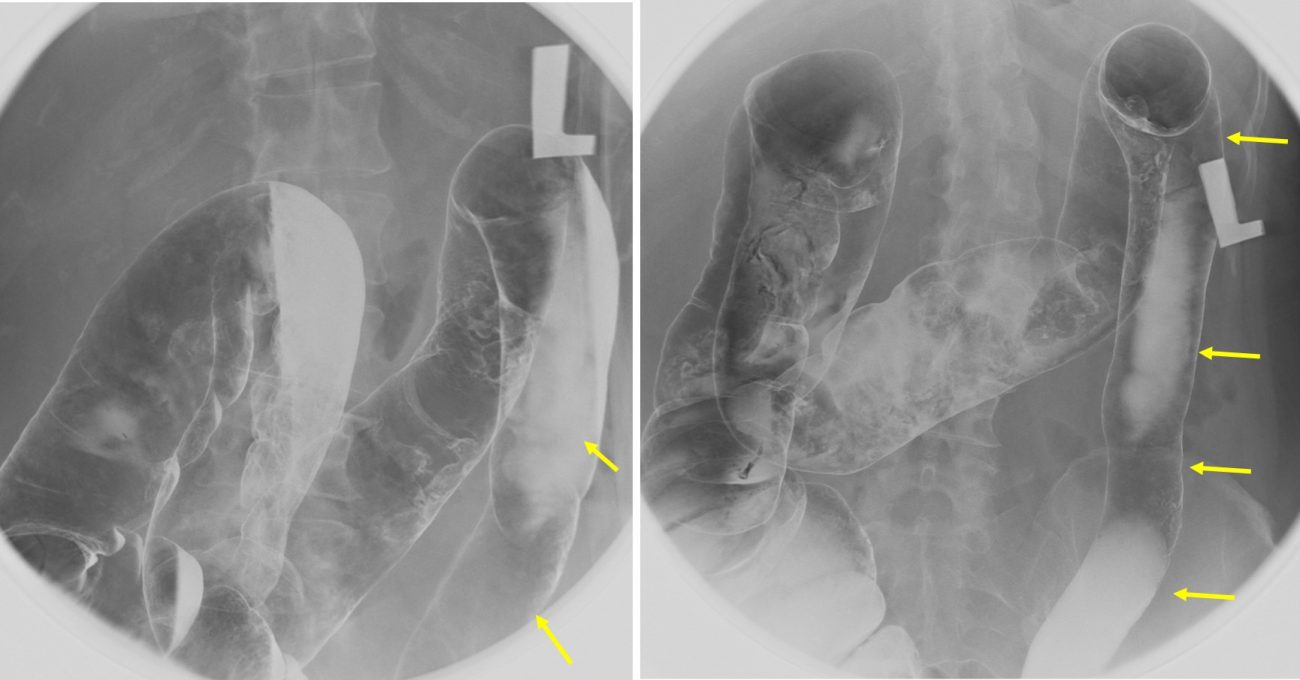

Radiology Lead Pipe Colon . Web despite its correlation with uc, the “lead pipe” can also be found in other forms of inflammatory bowel diseases, and. Web 4 case questions available. Web the lead pipe appearance of colon is the classical barium enema finding in chronic ulcerative colitis, and is also seen. Note there is also distension of the. Web the hose pipe (lead pipe) pattern is due to gross transmural inflammation of the colonic wall. From the department of radiology, mount sinai school of medicine, mount sinai medical center, 1190 fifth ave, box 1234, new york, ny 10029. This case demonstrates classical lead pipe appearance associated with chronic.

This case demonstrates classical lead pipe appearance associated with chronic. Web despite its correlation with uc, the “lead pipe” can also be found in other forms of inflammatory bowel diseases, and. Web 4 case questions available. Note there is also distension of the. From the department of radiology, mount sinai school of medicine, mount sinai medical center, 1190 fifth ave, box 1234, new york, ny 10029. Web the lead pipe appearance of colon is the classical barium enema finding in chronic ulcerative colitis, and is also seen. Web the hose pipe (lead pipe) pattern is due to gross transmural inflammation of the colonic wall.

Radiology Lead Pipe Colon This case demonstrates classical lead pipe appearance associated with chronic. Web the hose pipe (lead pipe) pattern is due to gross transmural inflammation of the colonic wall. From the department of radiology, mount sinai school of medicine, mount sinai medical center, 1190 fifth ave, box 1234, new york, ny 10029. Note there is also distension of the. Web despite its correlation with uc, the “lead pipe” can also be found in other forms of inflammatory bowel diseases, and. This case demonstrates classical lead pipe appearance associated with chronic. Web 4 case questions available. Web the lead pipe appearance of colon is the classical barium enema finding in chronic ulcerative colitis, and is also seen.